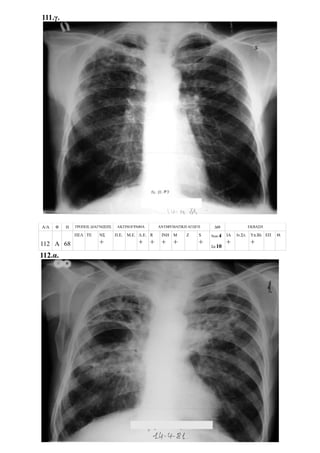

- Περιπτώσεις με επασβαστιωμένη πρωτοπαθή εστία και πρωτοπαθή συμπλέγματα 109

ΦΥΜΑΤΙΩΣΗ

Πρωτοπαθής εστία εν ενεργεία